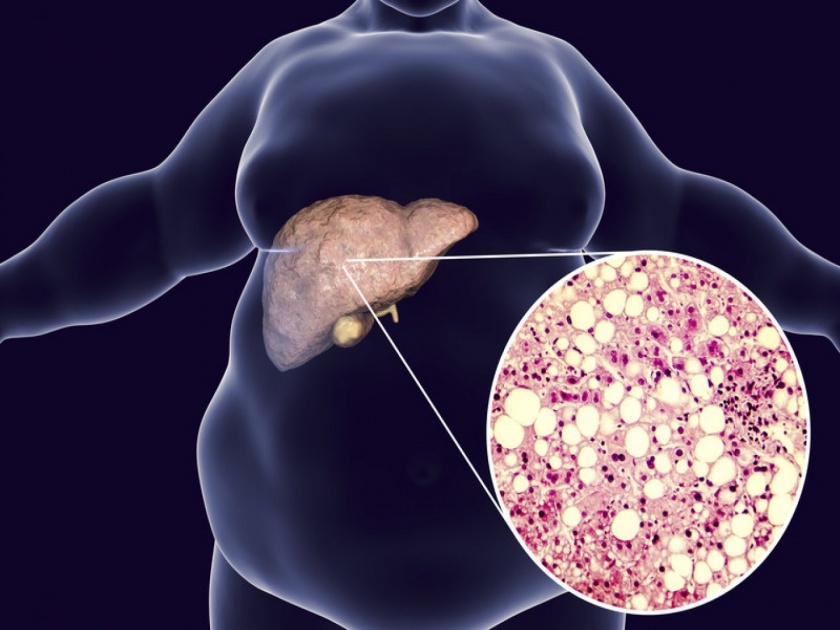

मानवी शरीराच्या वजनाच्या साधारणपणे २ टक्के वजन असणारे यकृत हे अवयव शरीरातील महत्त्वाचं अवयव आहे. याच यकृताला कोणत्या कारणामुळे आजार होतात याची माहिती घेणे आवश्यक आहे. असाच एक आजार म्हणजे फॅटी लिव्हर. जाणून घेऊया त्याची लक्षणे अन् उपाय.

फॅटी लिव्हर म्हणजे काय?

लिव्हरमध्ये काही प्रमाणात चरबी असणे ही सामान्य गोष्ट आहे, परंतू लिव्हरमधील चरबीचे प्रमाण लिव्हरच्या वजनाच्या साधारणपणे दहा टक्याने वाढल्यास फॅटी लिव्हर आजार उद्भवतो. अश्या परिस्थितीत, लिव्हरची काम करण्याची क्षमता कमी होते. त्याचे कार्य बिघडते आणि विविध लक्षणे दिसू लागतात. खरंतर लिव्हरवर परिणाम झाल्यानंतर बाह्य लक्षणे दिसून येण्यास बराच काळ जावा लागतो. आयुर्वेदात सांगितल्याप्रमाणे पित्त दोष हे फॅटी लिव्हरचे प्रमुख कारण आहे. शरीरात जास्त प्रमाणात पित्त तयार झाल्यामुळे दोष उत्पन्न होतो आणि लिव्हरचे कार्य बिघडण्यास सुरुवात होते.